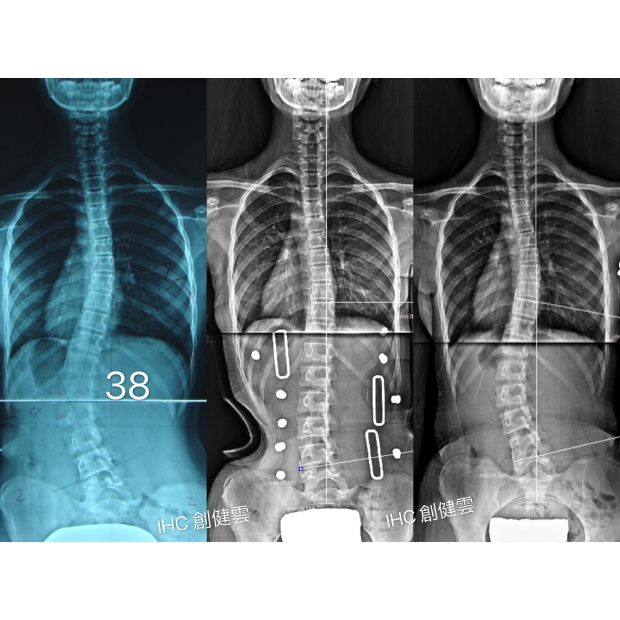

15歲重度脊椎側彎女孩

胸彎44度